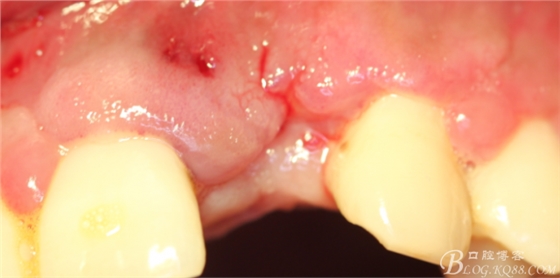

4個(gè)月后,唇側(cè)豐滿度尚可,與鄰牙之間齦乳頭完整。